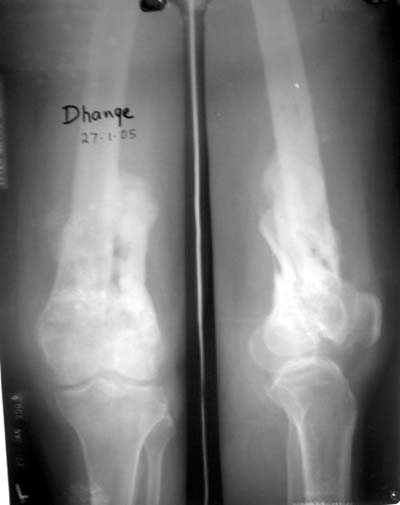

Качественные только исходные рентгенограммы (вышлю или завтра или в понедельник). Все последующие рентгенисследования были малоинформативны

(в т.ч. и последние снимки). КТ-исследование делалось 3 или 4 дня назад...

This is a coronal split in the femoral condyle and is a rare injury. Please see attachment for ORIF result

CT shows major bony fragments which are markedly rotated .With this amount of bony damage,you probably should attempt to get reasonably loooking knee with ORIF and thn if he needs a TKR due to pain a few years from now, then tleast you have something looking like a knee that you can replace rather than having to use revision knee for a primary TKR now. 4 weeks is not too long .what is the condition of soft tissues?

Before the CT and MRI era, we were treating the fractures with study of the Xrays alone. Such fractures with skeletal traction followed by non wtbearing mobilisation used to yield a fairly good range of movements. The CT gives a real ghastly picture of not so bad looking plain Xrays. I think this case needs traction to start with to correct the flexion deformity which probably will be achieved in 2 weeks time or less. We can then reassess the case with fresh Xrays. If possible one should try and fix the fragments to get some alignment. But the fixation should be stable enough to be able to mobilise the joint. Otherwise the traction can be continued for another 2 weeks to make the fracture sticky and then mobilise. We could get about 70 to 80* movements in spite of such communition. I am enclosing an Xray of a patient who is walking independantly and has 0 to 80* movemnts of the knee for the last one year

При внутрисуcтавных переломах трехмерные (3D) изображения, кроме красивого снимка, не дают полную информацию о состоянии отломков, самыми информативными являются корональные срезы на КТ и обычная длинная ренгенограмма конечности для сравнения оси конечности.

Фронтальные внутрисуставные переломы мыщельков бедра, так называемые Hoffa fracture, не частые, но встречающиеся переломы, в основном они связаны с травмой высокой энергией.